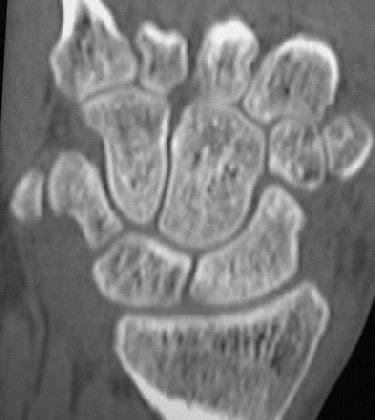

![]() |

| Nineteen-year-old man with wrist pain after fall. Coronal CT reconstruction of wrist shows no evidence of fracture. Image has been reversed to match image above. Groves AM, Cheow H, Balan K, Courtney H, Bearcroft P, and Dixon A, "16-MDCT in the Detection of Occult Wrist Fractures: A Comparison with Skeletal Scintigraphy" (AJR 2005; 184:1470-1474). |